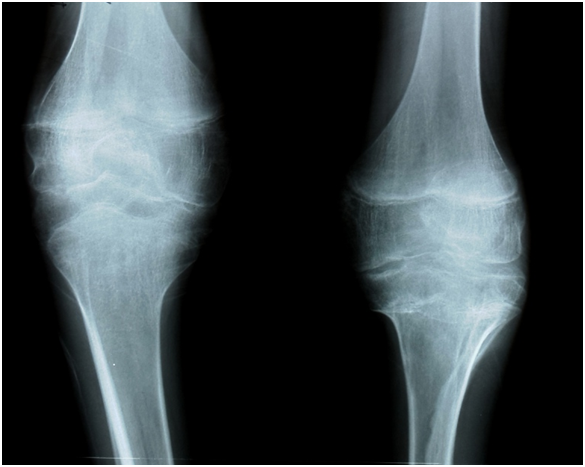

A male of 7 years, diagnosed with severe hemophilia at one year old. Hemarthrosis repetitive in his right knee for 3 years, with four episodes in last year. Last two hemarthrosis with minimal trauma. He maintained walking ability with right knee flexion and bending pelvis. Orthopedic reference was for lumbar pain since no other option for knee was given elsewhere. Clinical exam showed right knee to reach 85 degrees in flexion and 30 degrees in extension lag. Articular perimeter 37cm (5cm greater than the contralateral). Walking capable for few steps assisted on crutches in semi flexed right knee and shortening of 25mm. Radiographic classification as grade III arthropathy (Figure 1). Both physical therapy program and synoviorthesis help the patient to improve general quality of life and adapt himself to more independent life. Number of bleeding episodes decreased to one “slight” hemarthrosis in three years after treatment.

Figure 1 Inicial status of second patient. Seven years old male with acute insidious hemarthrosis of right knee.

A. Maximal passive flexion before treatment. B. Articular volumen increase incapable of complete extension. C. Radiographical changes corresponding to arthropaty grade III

This knee flexion noted painless mobility, but worsened to grade IV of hemophilic arthropathy on X rays (Figure 3).

Figure 3 Final follow up for second patient, worsen radiographical imagen to be classified as grade III arthropathy four years after synoviorthesis.